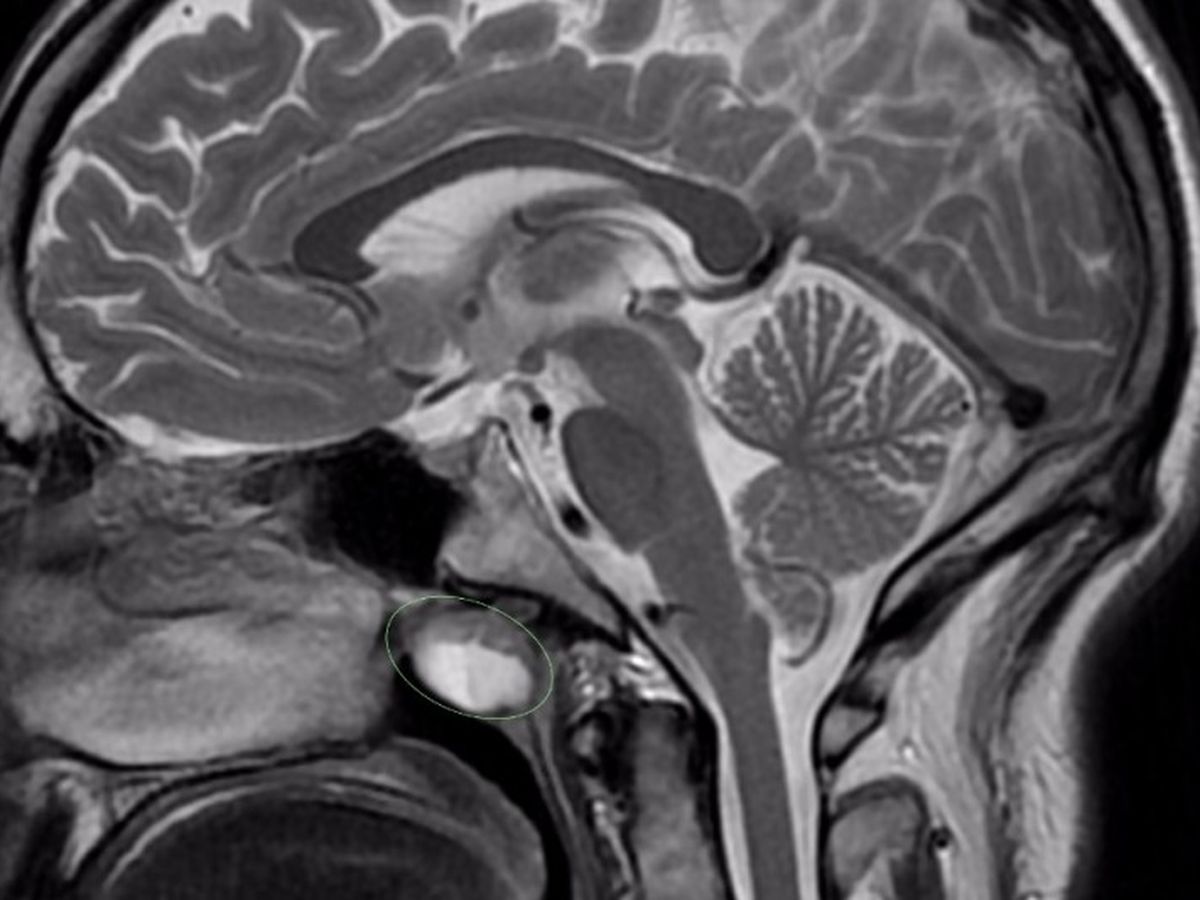

In Oct last year, I began getting sick, and after having an MRI on my head, the doctors found I have an "unusually large" (approximately 2cm) infected Thornwaldt cyst in my head, which is sandwiched between my nose and my brain (you can see it in the picture - the bright white blob) and it's causing me all kinds of havok at the moment, with symptoms like involuntary leg movements, feeling like my blood is boiling, extreme lethargy and dizziness, passing out, and even narcolepsy.